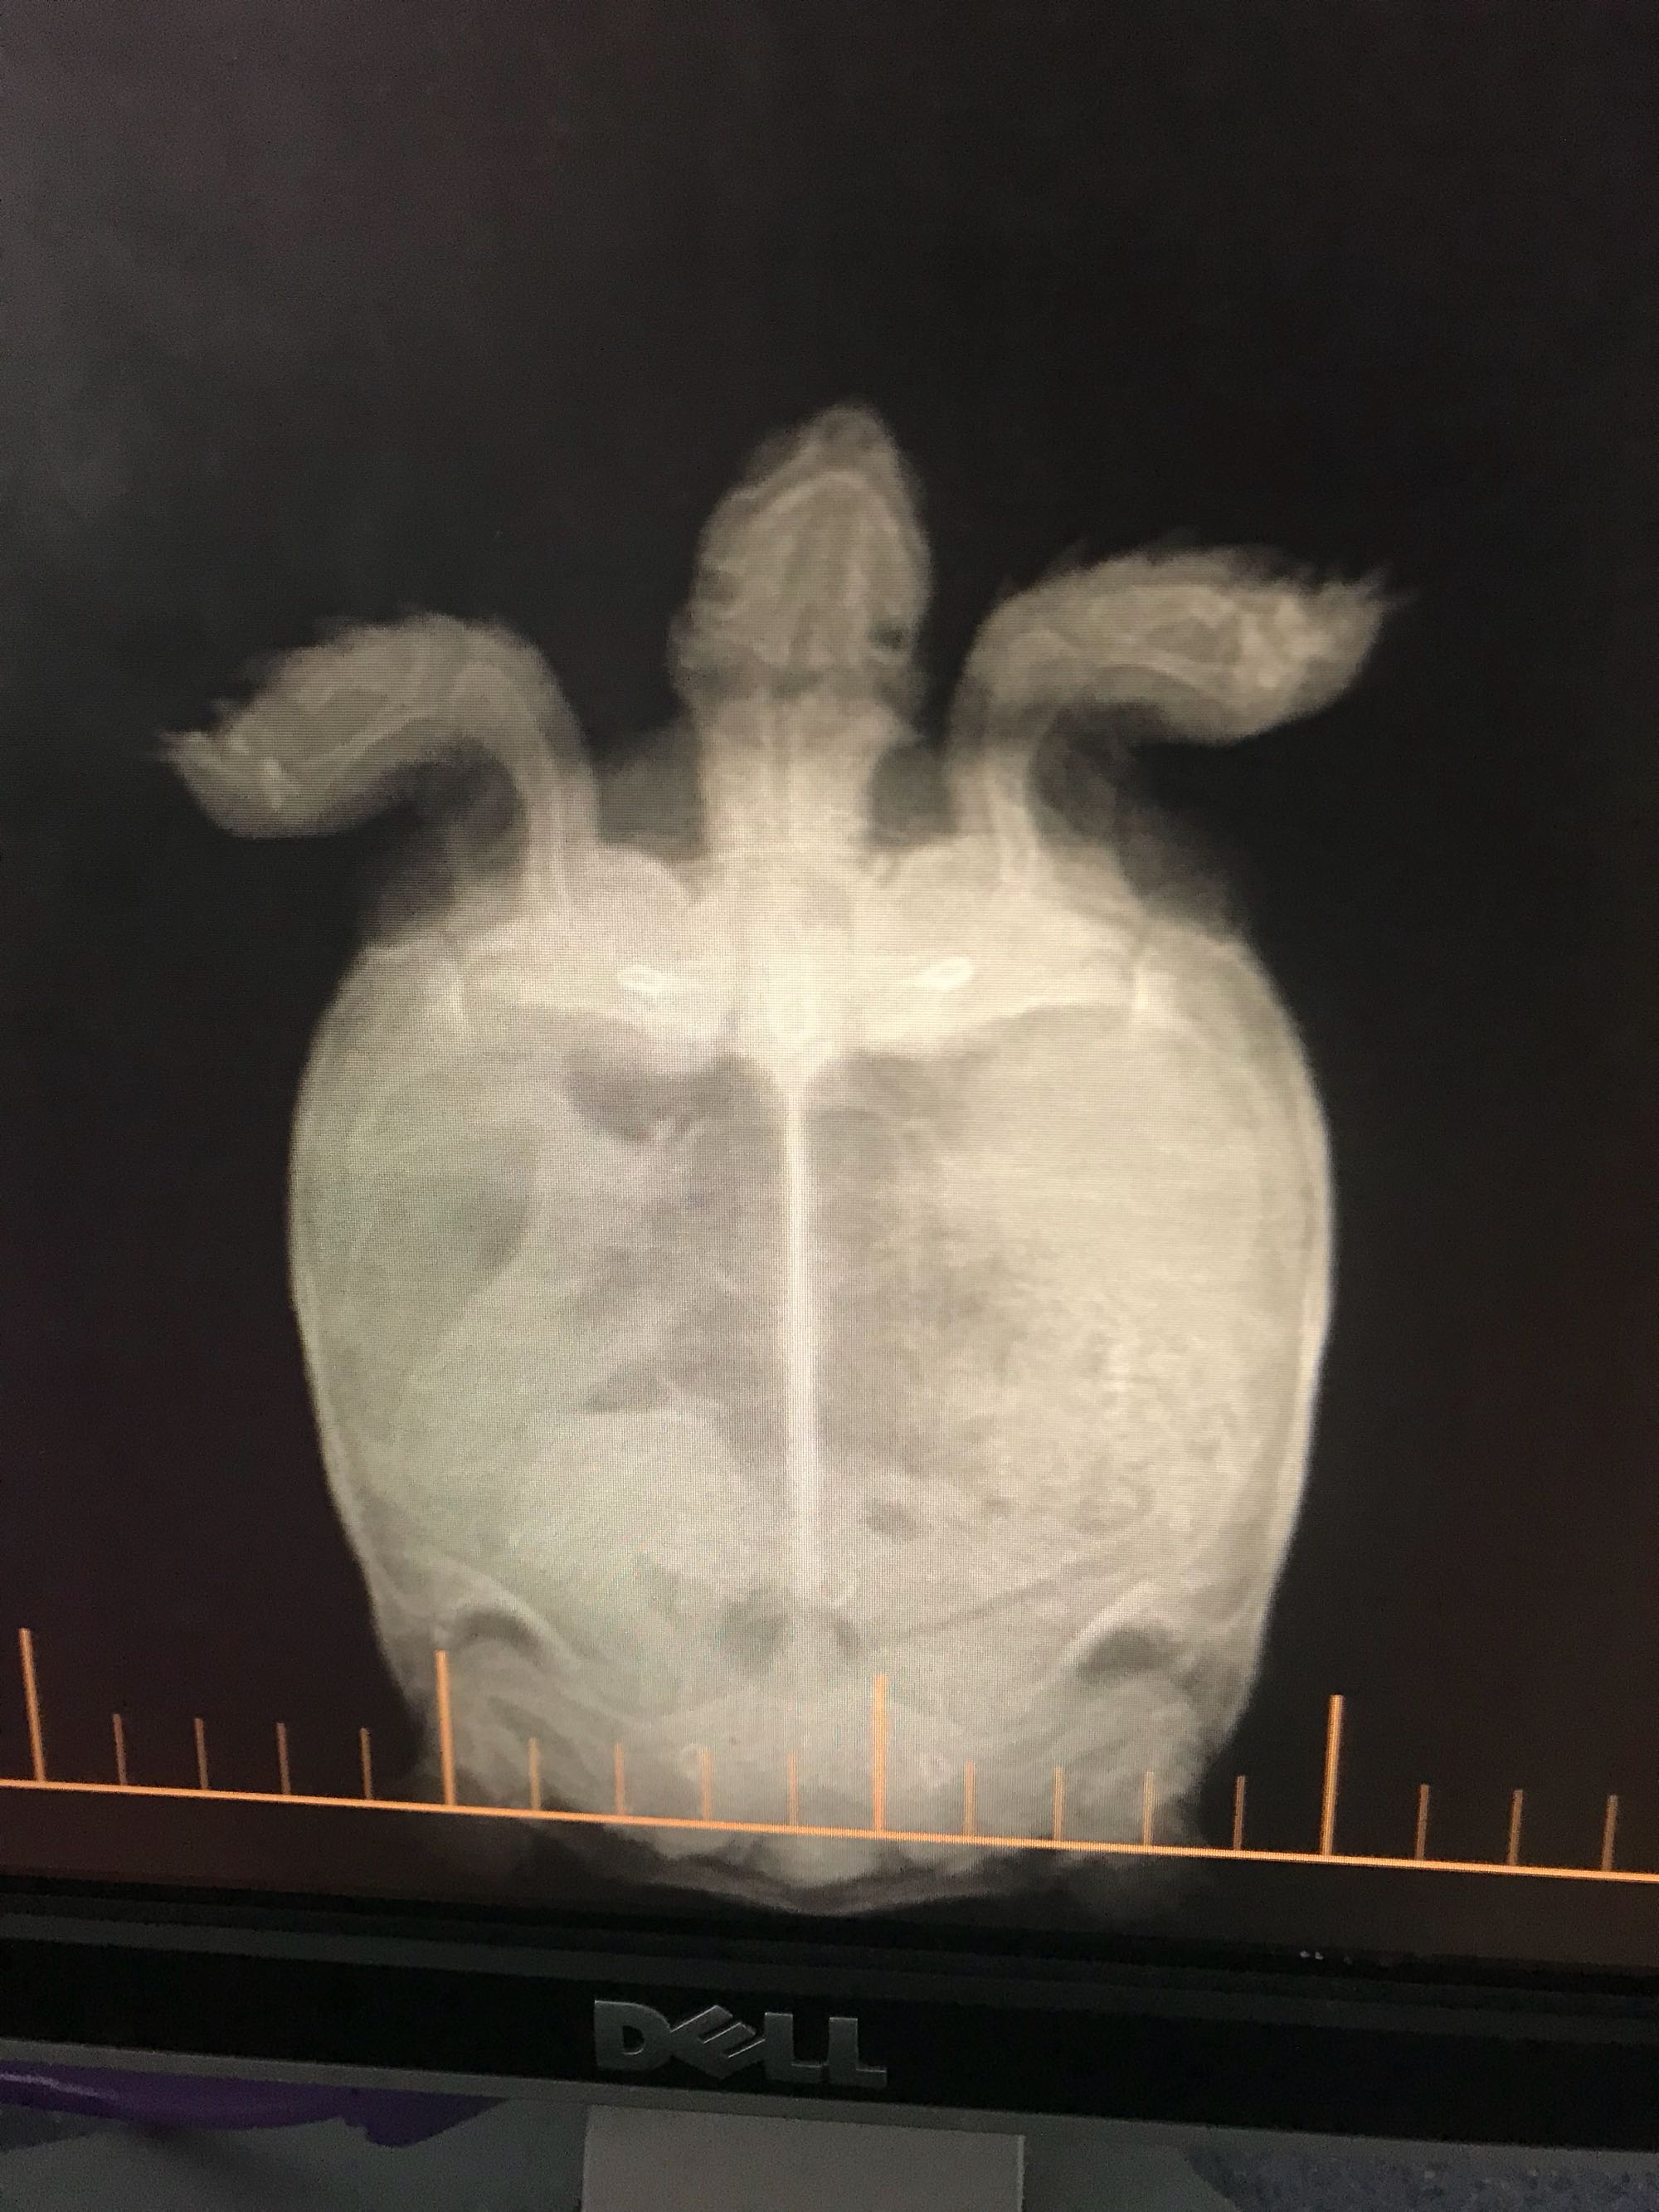

豆豆排酸史,每次两颗石头,前两颗是最近排的,后两颗是半年前排的

前两张是之前的,后一张是现在的,小的那个两个都排出去了,大的还是老样子